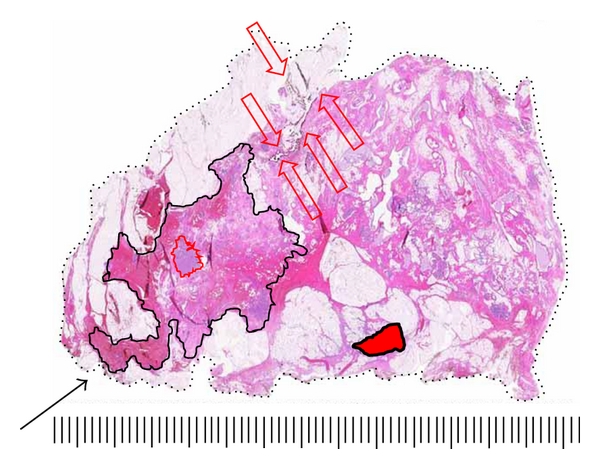

A typical case depicting tumor size and extent measurement and margin analysis using the LBP technique is shown in Figures 9 and 10. In this example, the 71-year-old patient presented with a palpable 1-2 cm nodule of the upper-inner quadrant. Mammogram showed a BIRADS 4 stellate density 14 mm in diameter corresponding to the palpable lesion. Ultrasonography disclosed an 15 mm hypoechoic lesion amenable to ultrasound-guided core needle biopsy, which was positive for grade 3 invasive ductal carcinoma. Presurgical MRI obtained for surgical planning purposes confirmed the presence of the biopsied lesion and additionally demonstrated a 60 mm area of enhancement extending anteriorly and superiorly from the index lesion. The patient was offered and accepted breast conservation surgery. The specimen was sectioned in the sagittal plane to correlate with MRI sagittal-reconstructed images and to best demonstrate extent of MRI enhancement and proximity to anterior, posterior, superior, and inferior margins. Gross examination of the specimen disclosed a firm 15 mm nodule; however, most of the enhancing 60 mm MRI-detected lesion consisted of clinically, surgically, and pathologically impalpable grade 3 DCIS. Final margin analysis reported DCIS present 2.0 mm from the anterior-superior margin. All other margins were >10 mm for DCIS and invasive carcinoma.

(a)

(b)

(c)

(d)